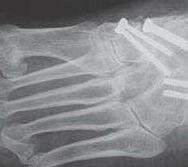

Alte Impressionsfraktur des Os cuboideum mit schweren Knorpelschäden.

Abbildung 9

Die isolierte Arthrose des Calcaneocuboidal-Gelenkes (CC-Gelenk) ist sehr selten. Mögliche Ursachen sind Traumen mit gewaltsamer Abduktion des Mittelfußes gegenüber dem Rückfuß. Der hierfür typische Unfallmechanismus wird meistens bei Zweiradfahrern vorgefunden 33. Impressionen der Gelenkfläche, Ausrisse des Processus anterior calcanei (Insertion des Ligamentum bifurcatum), sowie eine posttraumatische Instabilität des Gelenks können zu degenerative Veränderungen führen.